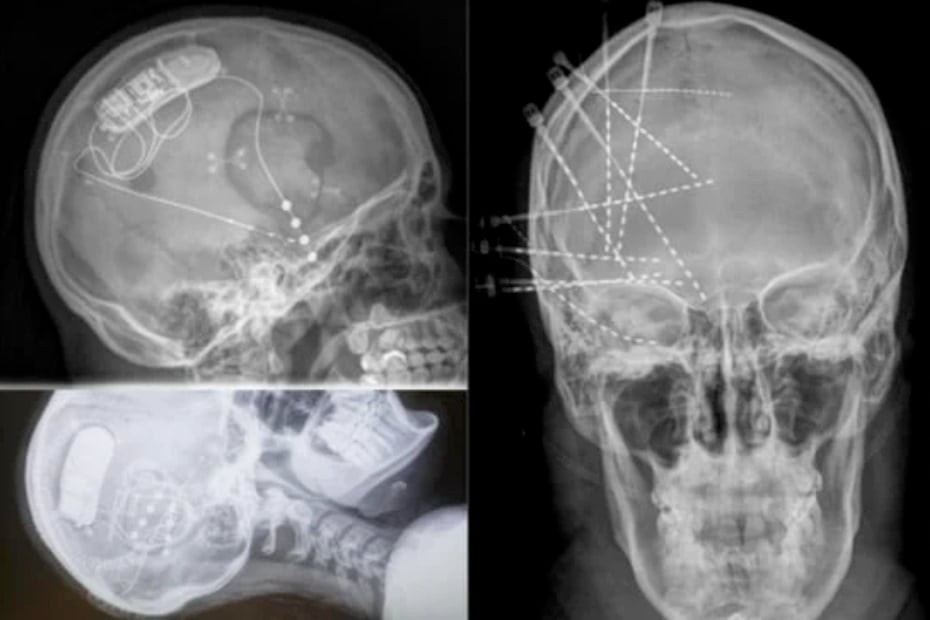

脳に埋め込んだ電極で「うつ状態」から「喜びに満ちた状態」へ感情を移行させることに成功

1月18日に『Nature Medicine』に掲載された論文によれば、脳内に埋め込んだ電極で「喜びの回路」を刺激することで、難治性のうつ病が数分で改善したとのこと。

信じがたい話ですが、論文が掲載された『Nature Medicine』は権威ある『Nature』系列の科学雑誌であり、信ぴょう性は確かなようです。